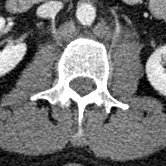

The fly-through doesn’t show the spinal injury very well, so here are some 2-D sections. The left panel is a section of my lumbar spine viewed from my left side; note the obviously smashed L3 vertebra. The middle panel is a top-view slide of L3, and the right panel is healthy L2 (the vertebra immediately above) for comparison.